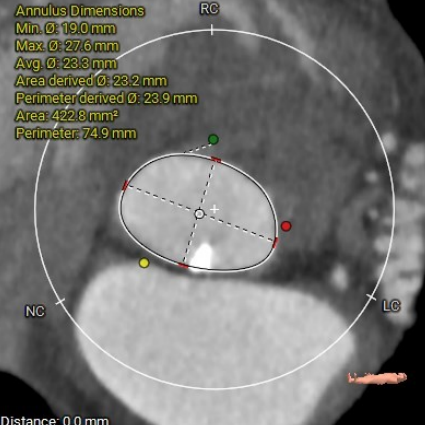

主动脉根部CT测量

瓣环周长:74.9mm

LVOT周长:83.1mm

法氏窦三窦直径

左冠状窦:31.5mm;右冠状窦:29.2mm;无窦:33.9mm

STJ高度:19.5mm

升主动脉平均直径:33.8mm

心脏角度:

49°

主动脉瓣钙化分布(钙化积分:950mm3)

左冠开口高度:

11mm

右冠开口高度:

16.2mm

● 主动脉根部:患者主动脉瓣为三叶瓣,左右冠窦可见部分粘连,重度钙化,瓣环到LVOT层面可见钙化,法式窦结构较大,左冠开口高度约11.0mm,右冠开口高度约16.2mm,STJ高度约19.5mm,直径约28.1mm,升主动脉未见明显扩张,心脏角度约49°,左室形态稍小,心肌增厚。